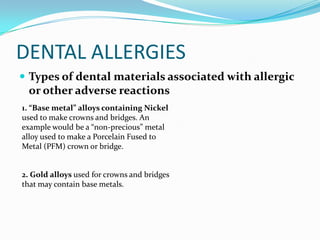

Dental Allergies What Are Those - Part 1

www.lechnerdentalgroup.com

www.lechnerdentalgroup.com

allergies dental